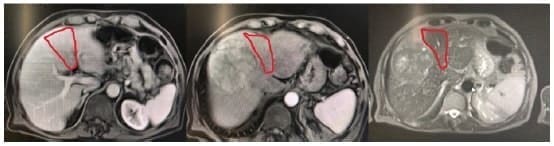

En la ecografía se encontró una masa de 9 cm en el lóbulo hepático derecho por lo que se realizó una Resonancia Nuclear Magnética (RNM) de abdomen contrastada que mostró un hígado no cirrótico con un hepatocarcinoma de 9 cm en los segmentos 4a, 5 y 8 (figura 1).

Figura 1. Resonancia nuclear magnética de abdomen. Se observa un hepatocarcinoma de 9 cm en el sector anterior derecho con compromiso parcial del segmento 4 (señalado en rojo).